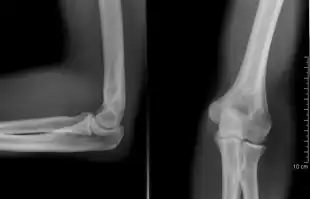

![]() Projectional radiography of the knee in a modern X-ray machine | |

Projectional radiography

The creation of images by exposing an object to X-rays or other high-energy forms of electromagnetic radiation and capturing the resulting remnant beam (or "shadow") as a latent image is known as "projection radiography". The "shadow" may be converted to light using a fluorescent screen, which is then captured on photographic film, it may be captured by a phosphor screen to be "read" later by a laser (CR), or it may directly activate a matrix of solid-state detectors (DR—similar to a very large version of a CCD in a digital camera). Bone and some organs (such as lungs) especially lend themselves to projection radiography. It is a relatively low-cost investigation with a high diagnostic yield. The difference between soft and hard body parts stems mostly from the fact that carbon has a very low X-ray cross section compared to calcium.